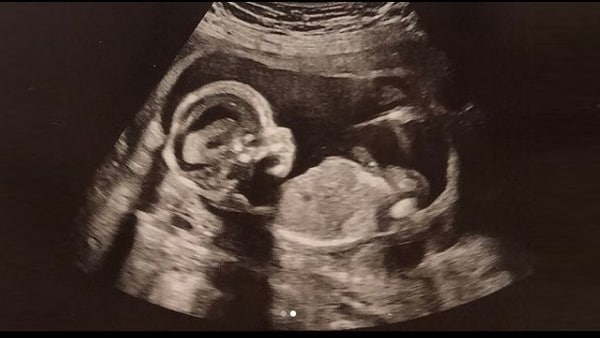

रिबेका ने अपनी खुशी और आश्चर्य को सोशल मीडिया पर शेयर करते हुए दिलचस्प कहानी से लोगों को वाकिफ करवाया है। उन्होंने सोशल मीडिया पर लिखा था कि 'डॉक्टरों के मुंह से ये सुनना कि आपके पेट में दो बच्चे पल रहे हैं, किसी शॉक से कम नहीं था। लेकिन, उसके बाद मैं और भी ज्यादा शॉक्ड तब हो गई, जब डॉक्टरों ने कहा कि दोनों बच्चों में तीन हफ्ते का अंतर है और ऐसा कैसे हुआ है, ये डॉक्टरों को भी समझ नहीं आ रहा है'

रिबेका 3 हफ्ते बाद फिर से कैसे प्रेग्नेंट हो गई ये समझ पाना डॉक्टरों के लिए भी आसान नहीं है। तमाम जांच के बाद डॉक्टर बस इतना कह पाए कि ये एक मेडिकल एग्जाम्पल है और ये कभी कभी ही हो सकता है। एबीसी न्यूज की रिपोर्ट के मुताबिक, रिबेका की प्रेगनेंसी को अलग तरीके से इलाज किया गया क्योंकि यहां एक साथ गर्भ में दो बच्चे पल रहे थे और दोनों में तीन हफ्ते का अंतर था, लिहाजा गर्भ के अंदर दोनों बच्चों का विकास में भी 3 हफ्ते का अंतर लगना था। लिहाजा, कोई भी दवाई दोनों बच्चों को एकसाथ ध्यान में रखकर ही दी जानी थी।